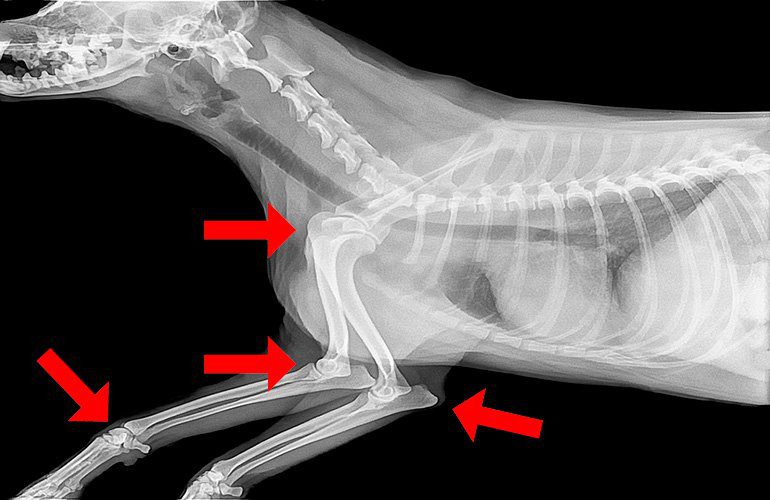

¿Qué es una articulación?

Una articulación es una zona anatómica de contacto entre dos huesos. Las articulaciones en general son móviles y, mediante el deslizamiento entre los huesos que la conforman, permiten el movimiento de las extremidades y otras áreas del cuerpo.

Para evitar que los huesos friccionen entre sí en cada movimiento, sus extremos están protegidos por cartílago articular, una estructura elástica y resistente que protege los huesos ante impactos.

Si las estructuras que forman la articulación comienzan a deteriorarse, se reduce el movimiento y se experimenta dolor. Por este motivo, es conveniente fortalecer las articulaciones del perro sano evitando que éstas degeneren prematuramente.